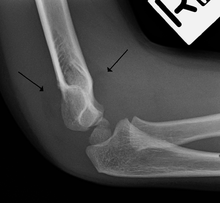

Fat pad sign

On an elbow X-ray, the fat pad sign, also known as the sail sign, suggests an occult fracture. Its name derives from the fact that it has the shape of a spinnaker (sail).[1] It is caused by displacement of the fat pad around the elbow joint. Both anterior and posterior fat pad signs exist, and both can be found on the same X-ray.

In children, a posterior fat pad sign suggests a condylar fracture of the humerus. In adults it suggests a radial head fracture. The fat pad sign only occurs after an intra-articular fracture.

The fat pad sign is invaluable in assessing for the presence of an intra-articular fracture of the elbow. An anterior fat pad is often normal. However a posterior fat pad seen on a lateral x-ray of the elbow is always abnormal. The patient will be unable to flex their elbow and requires orthopaedic input.[2]

The posterior fat pad is normally pressed in the olecranon fossa by the triceps tendon, and hence invisible on lateral radiograph of the elbow.[3] When there is a fracture of the distal humerus, or other pathology involving the elbow joint, inflammation develops around the synovial membrane forcing the fat pad out of its normal physiologic resting place. This is visible as the "posterior fat pad sign" and is often the only visible marker of a fracture, particularly in the pediatrics population.